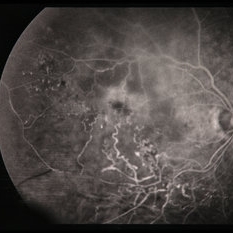

BRVO - Massive Exudate from Collaterals

Feb 24 2014 by David Callanan, MD

66-year-old female with BRVO - massive exudate from collaterals, 20/70 OD; 20/25 OS in 1985; +HTN, glaucoma; 20/200 OD 1987.

Condition/keywords: branch retinal vein occlusion (BRVO), collaterals, exudate